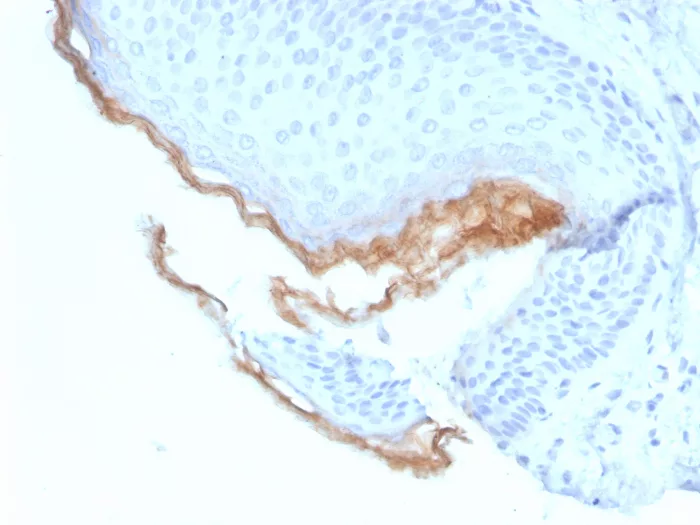

Immunohistochemistry (IHC)

1-2ug/ml

30 min at RT. Staining of formalin-fixed tissues requires heating tissue sections in 10mM Tris with 1mM EDTA, pH 9.0, for 45 min at 95°C followed by cooling at RT for 20 minutes

Human skin tissue (IHC). MCF-7 cell lysates.